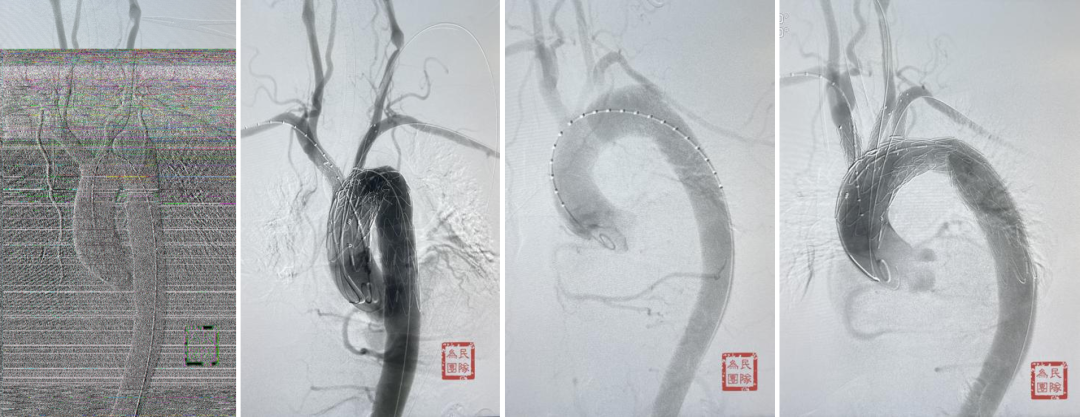

【原位三开窗技术】紧急情况的有效选择

原位三开窗技术是指在主体支架释放后,通过穿刺或烧灼在支架覆膜上开窗,重建分支血管血运的技术。

典型病例:一例TEVAR术后三个月发现内漏的患者,采用原位三开窗技术,依次开通左颈总动脉、头臂干、左锁骨下动脉。在有效脑保护下完成操作,术后七年随访效果理想。

另一例逆撕至头臂干的A型夹层患者,在ECMO辅助下行原位三开窗,术中虽出现心跳骤停,但通过ECMO模式转换成功救治,随访六七年CT显示良好。